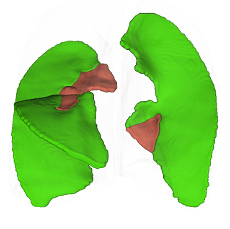

Lung Lobes

Anatomical segmentation

Pulmonary segments

Anatomical segmentation

Fissure completeness

Quantitative assessment